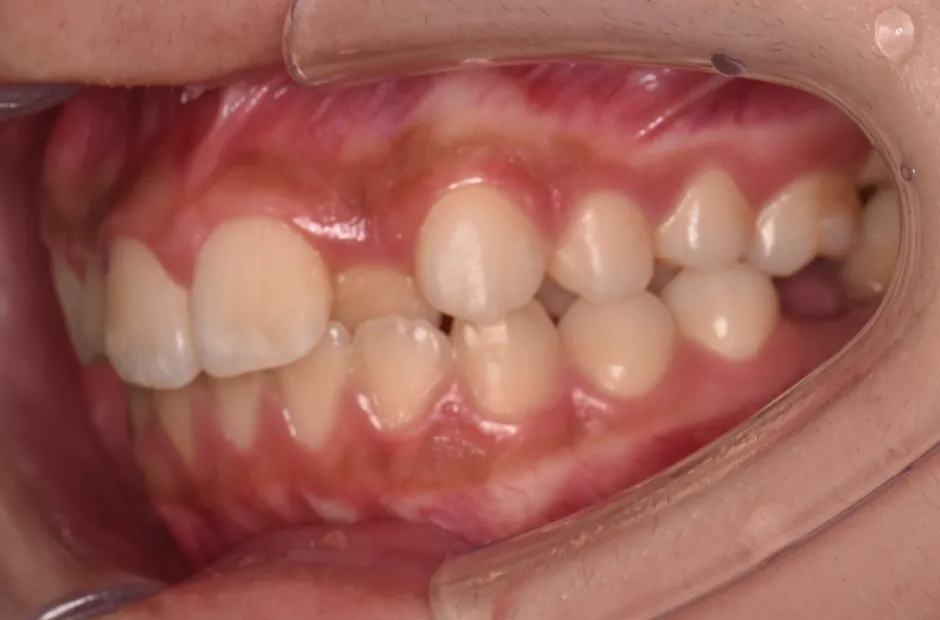

叢生

| 診断名・主訴 | 叢生 |

|---|---|

| 年齢・性別 | 43歳・女性 |

| 治療期間・回数 | 2年7か月 27回 |

| 治療に用いた主な装置 | 舌側矯正 |

| 抜歯部位 | 両顎4,4 |

| 治療費 | 100万円(税抜) |

| リスク・副作用 | 装置による違和感・疼痛・歯肉退縮・歯根吸収・虫歯のリスクなど |